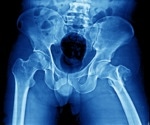

Study: Hip fracture cases estimated to nearly double by 2050